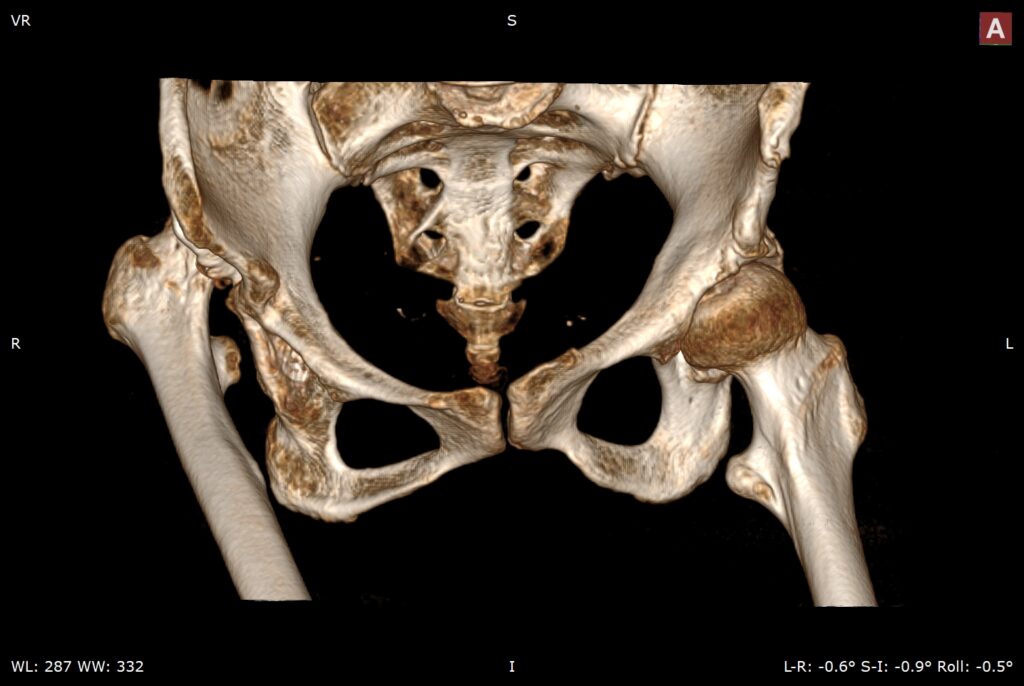

先天性髋关节脱位股骨头在假臼中再脱位(Congenital dislocation of the hip joint leads to re-dislocation of the femoral head in the false socket)